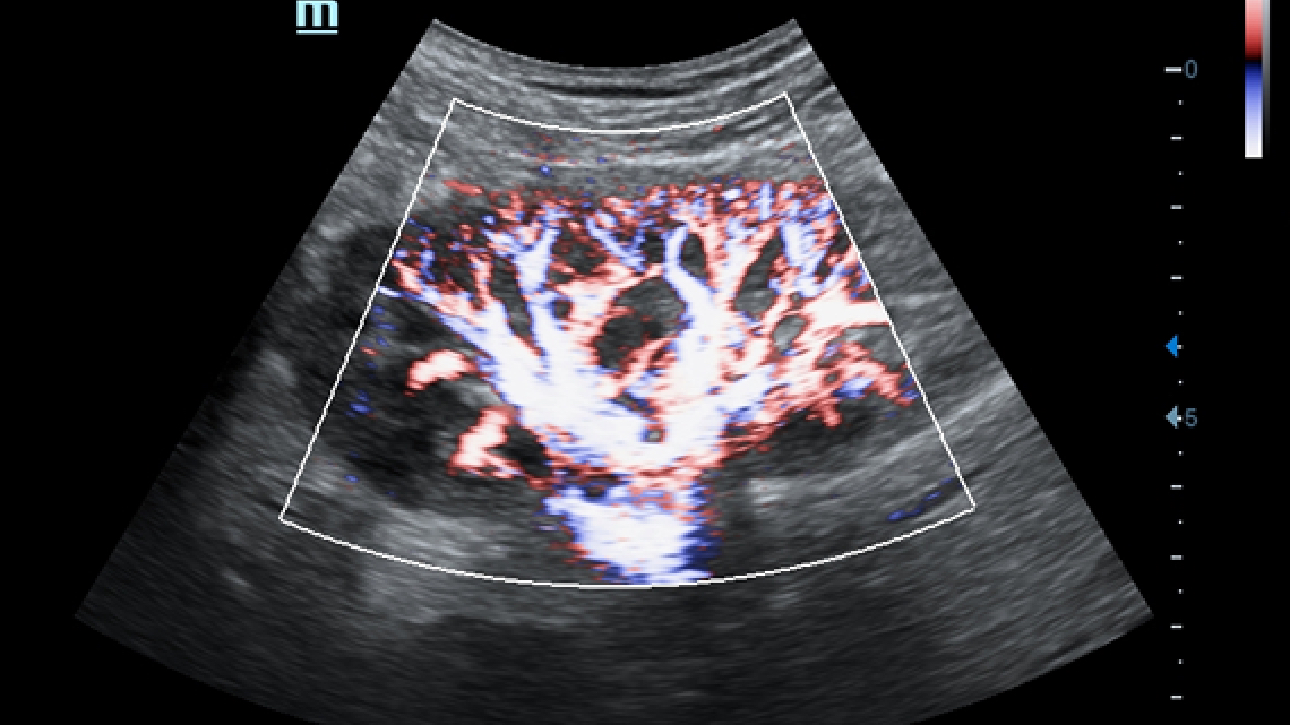

X-Insight is een inzichtelijke oplossing om meer visie te krijgen.

De gloednieuwe oplossing van Mindray is het geslaagde product dat is voortgekomen uit voortdurende klantinzichten in klinische behoeften in combinatie met steeds evoluerende, geavanceerde ultrasoundtechnologie?n. Vol energie en gebrand op toekomstgerichte inzichten en eindeloze mogelijkheden: dankzij de verhoogde schaalbaarheid wordt de oplossing continu verbeterd.

Als allround partner zet DC-60 Exp met X-Insight zich in om een allesomvattende oplossing te zoeken waarmee u alle aspecten van uw dagelijkse klinische activiteiten gemakkelijk en trefzeker kunt beheren.

De DC-60 Exp met X-Insight is ontworpen op basis van diepgaand inzicht in klantbehoeften om hoge effici?ntie met nauwkeurige beeldverwerking te leveren, dankzij eXacte helderheid, eXceptionele intelligentie en eXcellente ervaring.